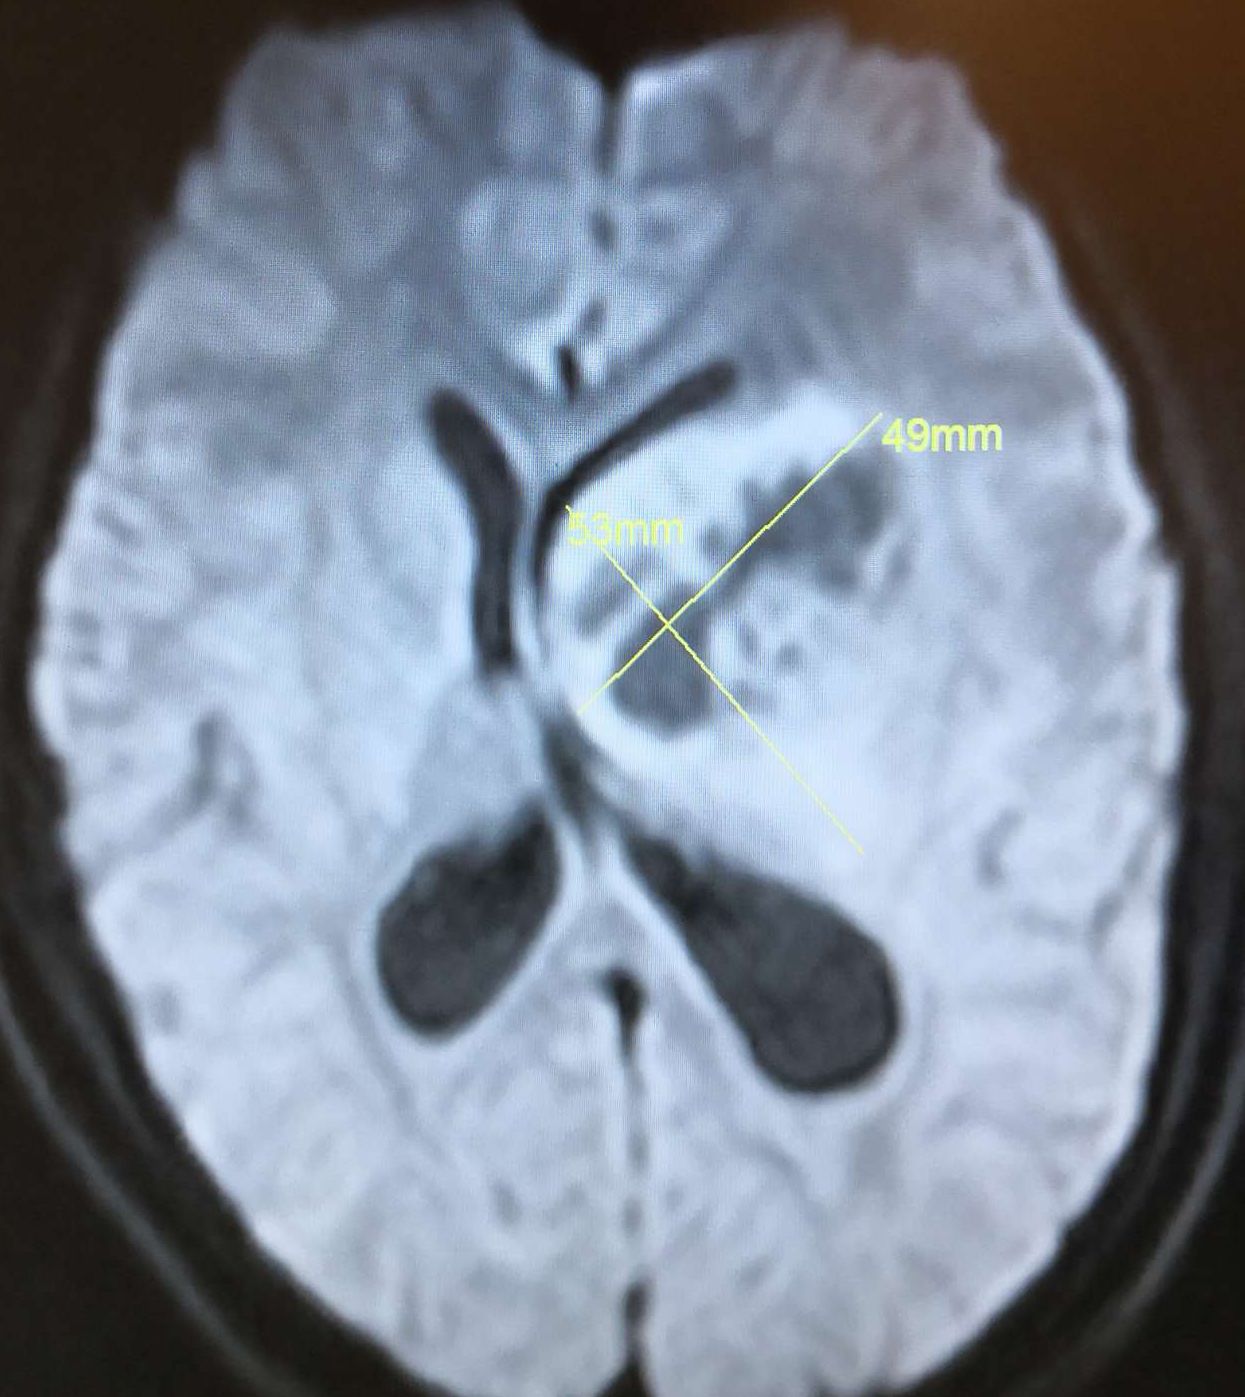

术前头颅MRI DWI显示:左侧基底节巨大占位病灶(49*53mm),呈高、低信号,脑室受压,中线移位明显。